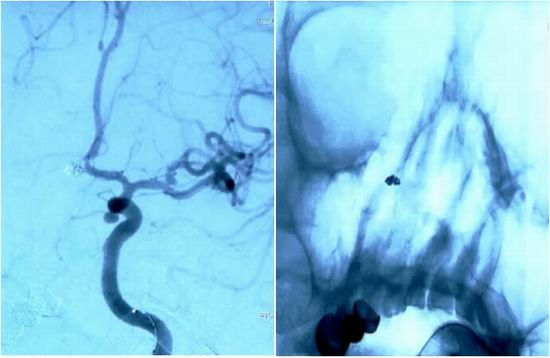

动脉瘤性蛛网膜下腔出血是一种死亡率和致残率极高的神经系统急危重症,院前死亡率高达10-15%,入院后也极易发生再出血和血管痉挛,引起患者重度残疾,甚至发生死亡。近日,我院神经内科医学部神经内一科联合放射介入科、麻醉与围术期医学科等科室成功救治一例颅内动脉瘤破裂